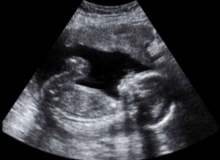

Gebelik Olmazsa Ne Zaman Doktora Gitmeli?

Toplum açısından hamile kalma süresi, 12 ay olarak kabul edilmektedir. Çünkü, fekondite denilen bir şey vardır. Yani sağlıklı bir çift için bir ayda döllenebilirlik oranı yüzde 25tir. Bu oran göz önüne alındığında, çiftlerin yüzde 85i 8-9 ay içinde